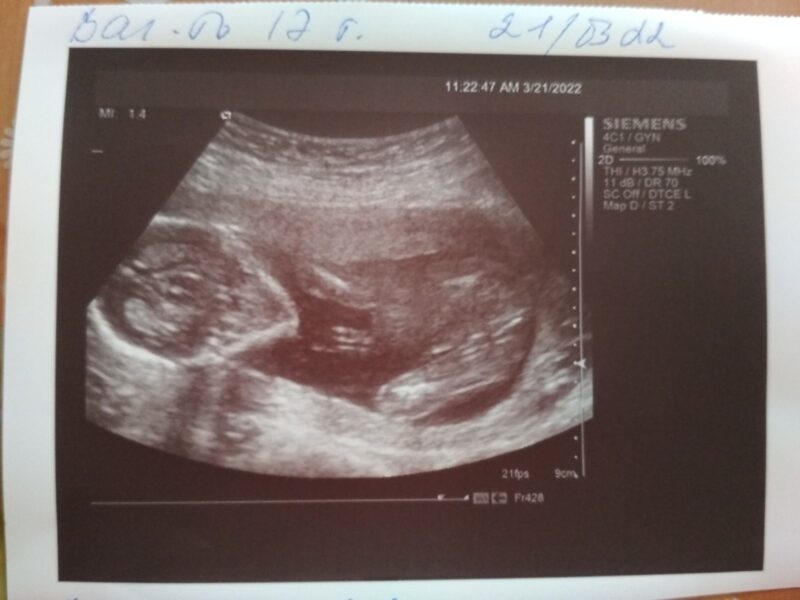

Juan, que la veía nerviosa frente al teléfono como ella no acostumbra, empieza a preguntarle si estaba pasando algo ya que estaba todo el tiempo pendiente del celular, mientras Silvina se preguntaba cómo hacer para decírselo. Finalmente luego de tanta insistencia de sospechar que algo le pasaba, deciden salir a caminar un rato y en medio de una playita mirando al lago Silvina le entrega su celular y le dice “mira” y le muestra la eco de Franchu, quien ya había cumplido tres meses de gestación

“Ahí no paraba de llorar, estaba totalmente conmovido, realmente no para de llorar, yo ya había llorado antes, hace tres meses con mis amigos”, cuenta Sil en una humorada que sonroja un poco a Juan pero que se hace cargo de que realmente esa noticia le cambió para siempre la vida. “Yo estaba desconsolado, no podía parar, era un llanto como de desahogo, donde me doy cuenta que este sueño se estaba comenzando a materializarse”.